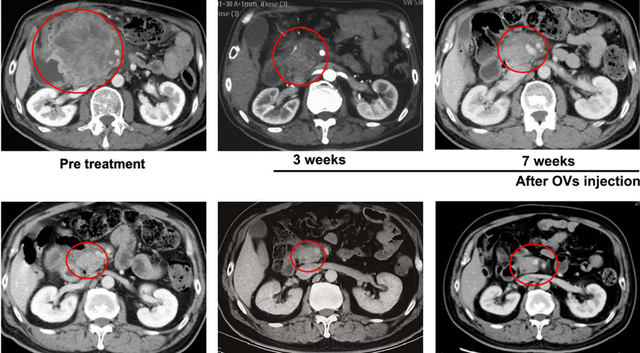

2024年7月,我国研究人员分享了一例结直肠癌巨大淋巴结转移经瘤内注射溶瘤病毒H101联合卡培他滨治疗后达到病理完全缓解的病例报告。

该患者为一位50多岁男性,2020年11月因右半结肠癌接受手术,术后未接受辅助化疗、靶向或免疫治疗。2022年2月起,患者出现体重下降、乏力、腹痛、食欲减退等全身症状,6月CT检查发现腹部一枚直径12厘米的巨大淋巴结转移灶,经活检确认为肠腺癌复发。考虑到患者对系统性治疗副作用的担忧,最终选择瘤内注射溶瘤病毒H101联合卡培他滨的治疗方案。

患者在首次瘤内注射溶瘤病毒H101后3-5天即出现腹痛缓解和体位改善,第二次注射时肿瘤质地已明显变软。治疗3周后(2022年8月8日),CT显示肿瘤从12厘米缩小至4.5厘米,之后持续退缩,至第18周(2022年11月29日)几乎消失。截至2024年2月随访,无复发,无进展生存期达19个月。